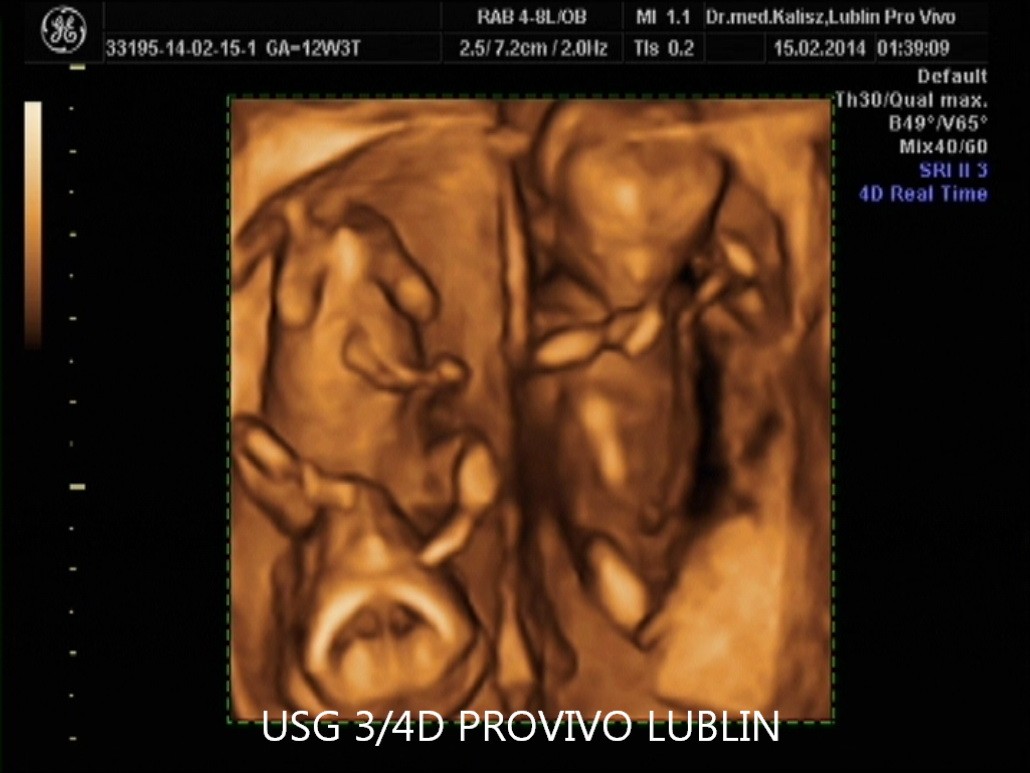

USG 3D daje możliwość trójwymiarowej rekonstrukcji obrazu płodu oraz wnętrza macicy. Dzięki temu można zobaczyć powierzchnię zewnętrzną ciała dziecka, a twarz płodu staje się znacznie wyraźniejsza niż w klasycznym badaniu 2D. To badanie szczególnie cenione przez rodziców, którzy chcą zobaczyć dziecko jeszcze przed porodem w bardziej realistyczny sposób. Na obecnej stronie PROVIVO wskazano również, że rodzice otrzymują zapis badania w formie elektronicznej.

USG 4D Lublin – obraz dziecka w czasie rzeczywistym

USG 4D pokazuje obraz podobny do badania 3D, ale dodatkowo rejestruje go w czasie rzeczywistym. Oznacza to, że rodzice mogą obserwować ruchy dziecka, mimikę twarzy i zachowanie płodu niemal jak podczas podglądu na żywo.

Na stronie PROVIVO wskazano, że badanie może być wykonane między 11. a 14. tygodniem ciąży, a następnie około 20. lub 30. tygodnia ciąży. To właśnie w tych okresach można uzyskać wartościowe obrazy płodu i lepiej ocenić jego rozwój.